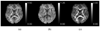

This article presents two related advancements to the diffusional kurtosis imaging estimation framework to increase its robustness to noise, motion, and imaging artifacts. The first advancement substantially improves the estimation of diffusion and kurtosis tensors parameterizing the diffusional kurtosis imaging model. Rather than utilizing conventional unconstrained least squares methods, the tensor estimation problem is formulated as linearly constrained linear least squares, where the constraints ensure physically and/or biologically plausible tensor estimates. The exact solution to the constrained problem is found via convex quadratic programming methods or, alternatively, an approximate solution is determined through a fast heuristic algorithm. The computationally more demanding quadratic programming-based method is more flexible, allowing for an arbitrary number of diffusion weightings and different gradient sets for each diffusion weighting. The heuristic algorithm is suitable for real-time settings such as on clinical scanners, where run time is crucial. The advantage offered by the proposed constrained algorithms is demonstrated using in vivo human brain images. The proposed constrained methods allow for shorter scan times and/or higher spatial resolution for a given fidelity of the diffusional kurtosis imaging parametric maps. The second advancement increases the efficiency and accuracy of the estimation of mean and radial kurtoses by applying exact closed-form formulae.